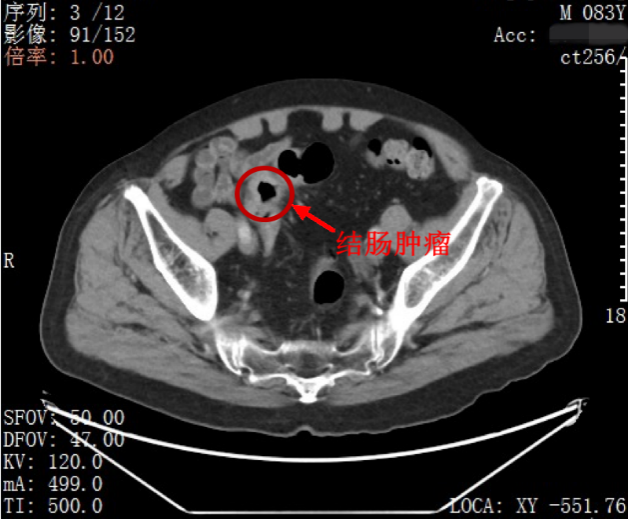

多方了解之后,家人带着叶先生来到北大深圳医院胃肠外科就医,通过进一步完善检查,科室主任吕国庆医生与团队详细分析了叶先生的病情:一是患者的两处肿瘤并没有关联,均为独立的原发肿瘤,没有发生肿瘤转移。病理结果提示:患者胃部的不规则溃疡为中期管状腺癌;乙状结肠则有一个 4.9 厘米×4.5 厘米大小的中期腺癌。叶先生两处肿瘤均未发生转移,还有手术切除的机会。

吕国庆主任带领包括敖胜医生、李冠医生在内的手术团队,仅在叶先生的肚脐部位切开了 1 个约 4 厘米的切口和 4 个几毫米的小孔,采用 3D 腹腔镜,先是切除了胃部的肿瘤,并将切除的组织从脐部切口取出;再用 3D 腹腔镜深入乙状结肠,切除肿瘤,从脐部切口取出切除的组织,最后吻合肠道,缝合脐部切口。手术过程顺利,4 小时完成,术中几乎无出血。